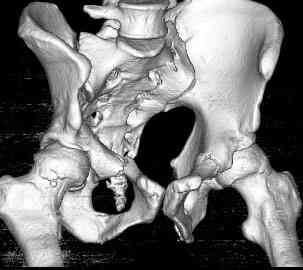

Уважаемые коллеги! опять вопрос по повреждению таза. Больной получил производственную травму 10 дней назад - удар балкой около 3 тонн в область верхней трети правого бедра и лона.

Был диагностирован перелом "типа бабочки" и повреждение уретры. Сделана цистостома. У насв отделении 3 дня. Имеется огромная флюктуирующая гематома с "галифе"-образной деформацией обеих бедер. Пнкционно эвакуировали в несколько приемов из подфасциальных полостей на бедрах около 3 литров геморрагического отделяемого с последующей эластической компрессией. При пункциях выявлено сообщение полостей на бедрах - видимо через поравннуюдиафрагму дна и полость таза - при удалении крови справа уменьшался объем левого бедра. Какой то активности проявялять покабоимся - аппаратная фиксация через отслоенные ткани представляется чреватой нагноением, открытая фиксация в условиях такой гематомы тоже не радует. Хотелось бы услышать ваше мнение

можно полечить в 2 этапа:как правило в области гребней гематомы все же не бывает, если гребни "свободны", то можно ограничиться на первом этапе передней рамой, вводя стержни через них (повреждение ротационно-нестабильное), затем после лечения отслаивающего повреждения Morel-Lavallee, выполнить открытую репозицию, внутреннюю фиксацию, возможно вместе с урологами. Тактику возможного лечения этой

Следующим этапом через 5-6 дней приступаем к фиксацию повреждения таза, иначе прооперериванные на фоне Morel-Lavallee повреждения осложняются инфицированием послеоперационной раны.